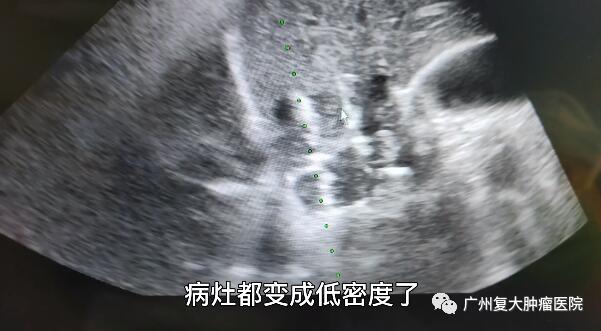

入院后,患者完善相关检查。结合患者病史,为进一步控制肿瘤生长,减轻肿瘤负荷,延长患者生命,再次明确肿瘤类型,方便下一步指导用药。经患者及家属理解与同意后,在超声影像引导下,我院牛立志院长为其实行肝脏肿瘤穿刺活检及不可逆电穿孔消融术。“病灶变成低密度,表明肿瘤得到一个比较完全的消融。”